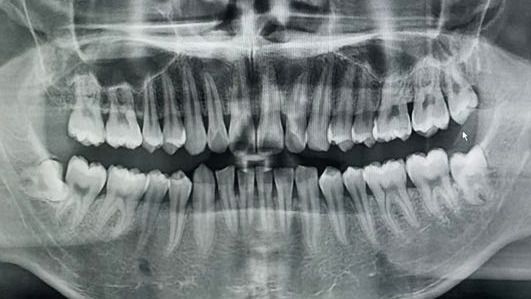

跟住就係醫生檢查治療,照完CT,果個醫生檢查完後,就話係阻生齒,最好剝咗佢,唔係嘅話,就會頂壞隔離嘅牙。我又一次問價錢,因為好多人都話大陸裡邊會亂加錢,醫生就話係千二蚊,同之前報價一樣,我霖咗下,就決定俾佢剝。